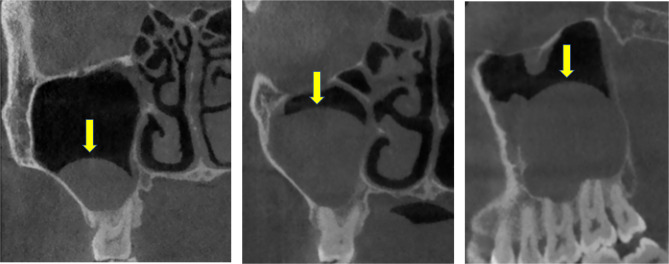

Background and objective: There are still many controversies about the factors influencing maxillary sinus cysts and their clinical management. This study aims to construct a prediction model of maxillary sinus cyst and explore its clustering pattern by cone beam computerized tomography (CBCT) technique and machine learning (ML) method to provide a theoretical basis for the prevention and clinical management of maxillary sinus cyst.

Methods: In this study, 6000 CBCT images of maxillary sinus from 3093 patients were evaluated to document the possible influencing factors of maxillary sinus cysts, including gender, age, odontogenic factors, and anatomical factors. First, the characteristic variables were screened by multiple statistical methods, and ML methods were applied to construct a prediction model for maxillary sinus cysts. Second, the model was interpreted based on the SHapley Additive exPlanations (SHAP) values, and the risk of maxillary sinus cysts was predicted by generating a web page calculator. Finally, the K-mean clustering algorithm further identified risk factors for maxillary sinus cysts.